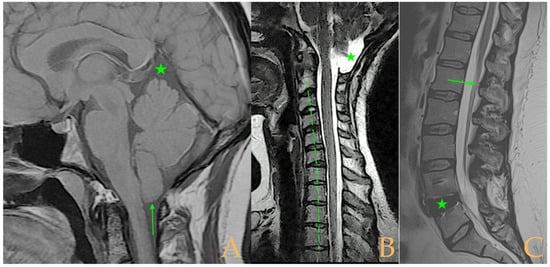

The MRI showed a descent of the cerebellar tonsils, increased supracerebral space, and micro lacunae in the bilateral white matter and the left basal ganglia. Upper cervical kyphosis and straightening in the lower levels. Surgical arthrodesis at C4-C5 and C5-C6. Cervical, thoracic and lumbar protrusions. Ischemia and oedema in the cervical and thoracic spinal cord. Slight cervical rotoscoliosis. Disc protrusions: T7-8, T11-L1, L2-L3-L4, and disc herniation L4-L5. Loss of the lumbar lordosis. Conus medullaris at the level of the middle third of the L1 vertebra (Figure 2). The X-ray images of the entire spine showed levoconvex thoracolumbar scoliosis of 21°, dysmetria of the lower extremities with shortening of the right lower extremity by 10 mm, with respect to the level of the hip, and 99 mm at the level of the iliac crests, 16° cervical lordosis, 49° thoracic kyphosis, and 59° lumbar lordosis.

Figure 2. Imaging of patient 2. A: Image suggestive of spinal cord ischemia (arrows), impaction of the cerebellar tonsils (star), and straightening of the cervical spine (interrupted line); B: straightening of the upper part of the lumbar spine (interrupted line) and conus medullaris at the level of the L2L3 disc space (arrow); and C: brain MRI with micro lacunae in the white matter (arrows).